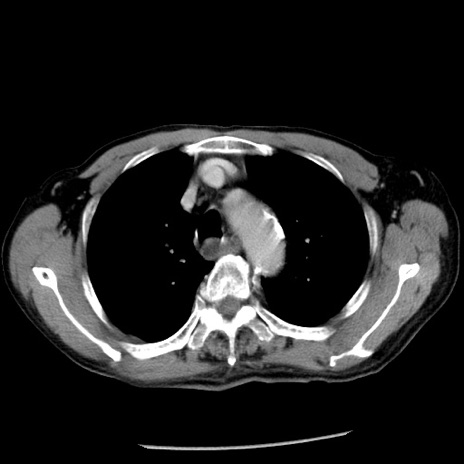

症例26(横断像)

【症例】80歳代男性

【主訴】嘔吐

【現病歴】昨晩2回嘔吐あり、今朝になっても嘔吐あり。来院。

【既往歴】胃潰瘍

【身体所見】意識清明、BT 37.6℃、BP 166/95mmHg、HR 100bpm、SpO2 97%、腹部:平坦・軟、腸蠕動音聴取良好、圧痛なし。

【データ】WBC 21900、CRP 1.46